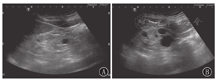

ADPKD是全球发病率最高的单基因遗传性肾病,其发病率为1 /1 000~1 /400,主要是由位于第16号染色体上的PKD1和第4号染色体上的PKD2基因突变引起,有家族史,多于成年后发病,且预后不良,儿童发病少见[10]。ADPKD是一种以器官内囊肿形成为特征的全身性疾病[19],可多器官受累,因此常合并多囊肝、多囊脾、多囊胰等。肾脏的主要病理学改变为肾小管上皮细胞来源的充满液体的囊泡不断形成和扩张,最终与集合管连接不良,尿液排出受阻引起肾小管形成潴留性囊肿,进行性增大,肾脏表面及内部可见大小不等的肉眼可见的囊肿,肾实质残留很少。病变为双侧。患儿年幼时肾脏外形、大小正常或略增大,随着年龄增长,肾内囊肿的大小和数目不断地增大、变多,多数患者40~50岁时肾脏才会出现症状。儿童ADPKD双侧肾脏改变多不典型,超声表现为双肾大小正常或稍大;肾脏的超声表现多数正常或难以断定,肾实质内可见数个囊肿聚集或呈散在分布,囊肿较小、较少,肾实质回声可见;肾盂肾盏均保持正常形态,肾窦未见受压,随着年龄的增长及病情进展,囊肿逐渐增大、增多,囊肿间彼此不相通,囊壁可见成团成簇的强回声点,双肾明显增大,形态失常,表面凹凸不平,肾实质变少(图3)。对于疑似ADPKD患儿,临床应询问家属是否有家族史,综合分析得出诊断。若实际情况需要则应告知患儿要定期复查,随访观察肾内囊肿的发展变化。

2016版世界卫生组织(WHO)肾肿瘤分类将旧版中肾母细胞瘤名下的CPDN与肾母细胞瘤列为并列的亚类,增加了儿童CN这一亚类[26]。两者均无家族史,一般不伴其他异常,临床症状无特异性,通常无症状,幼儿多为腰腹部触及或临床体检时偶然发现包块就诊,其影像学检查及大体标本上也相似,鉴别须行病理镜检。CPDN和CN的主要鉴别依据是前者的间隔内含有胚芽成分和不成熟组织,而后者没有。CPDN 1975年由Brown首次提出,至今国内外报道甚少[27],多发生于2岁以内男童,左肾多于右肾,肿瘤通常较大[28]。CPDN与儿童CN均为多房囊性肿物,局限于同侧肾脏的一部分,与肾组织间仅一层薄膜相隔,未受累肾组织正常。CPDN和CN的超声图像类似,无法鉴别,其共同超声影像学特点多为单侧肾脏受累,肾脏的某一部位可见一单发的含有较多纤细分隔的囊性肿物,多为类圆形或椭圆形,边界清晰,有包膜,囊内均为无回声,囊壁及分隔上均无血流信号,未受累区肾脏组织正常(图5)。